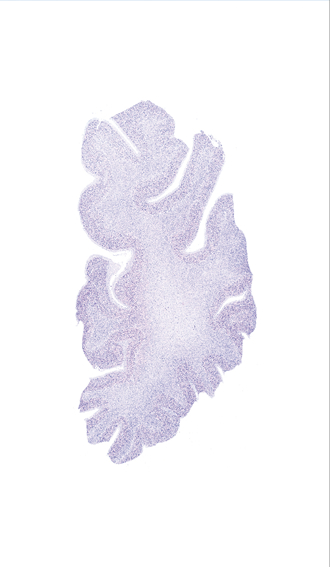

Frontal sections (Nissl) from the Atlas Brain:

Macroscopy

Microscopy

Slice ID:

r1-0050

Plate NR:

05

Position:

-34,5 mm